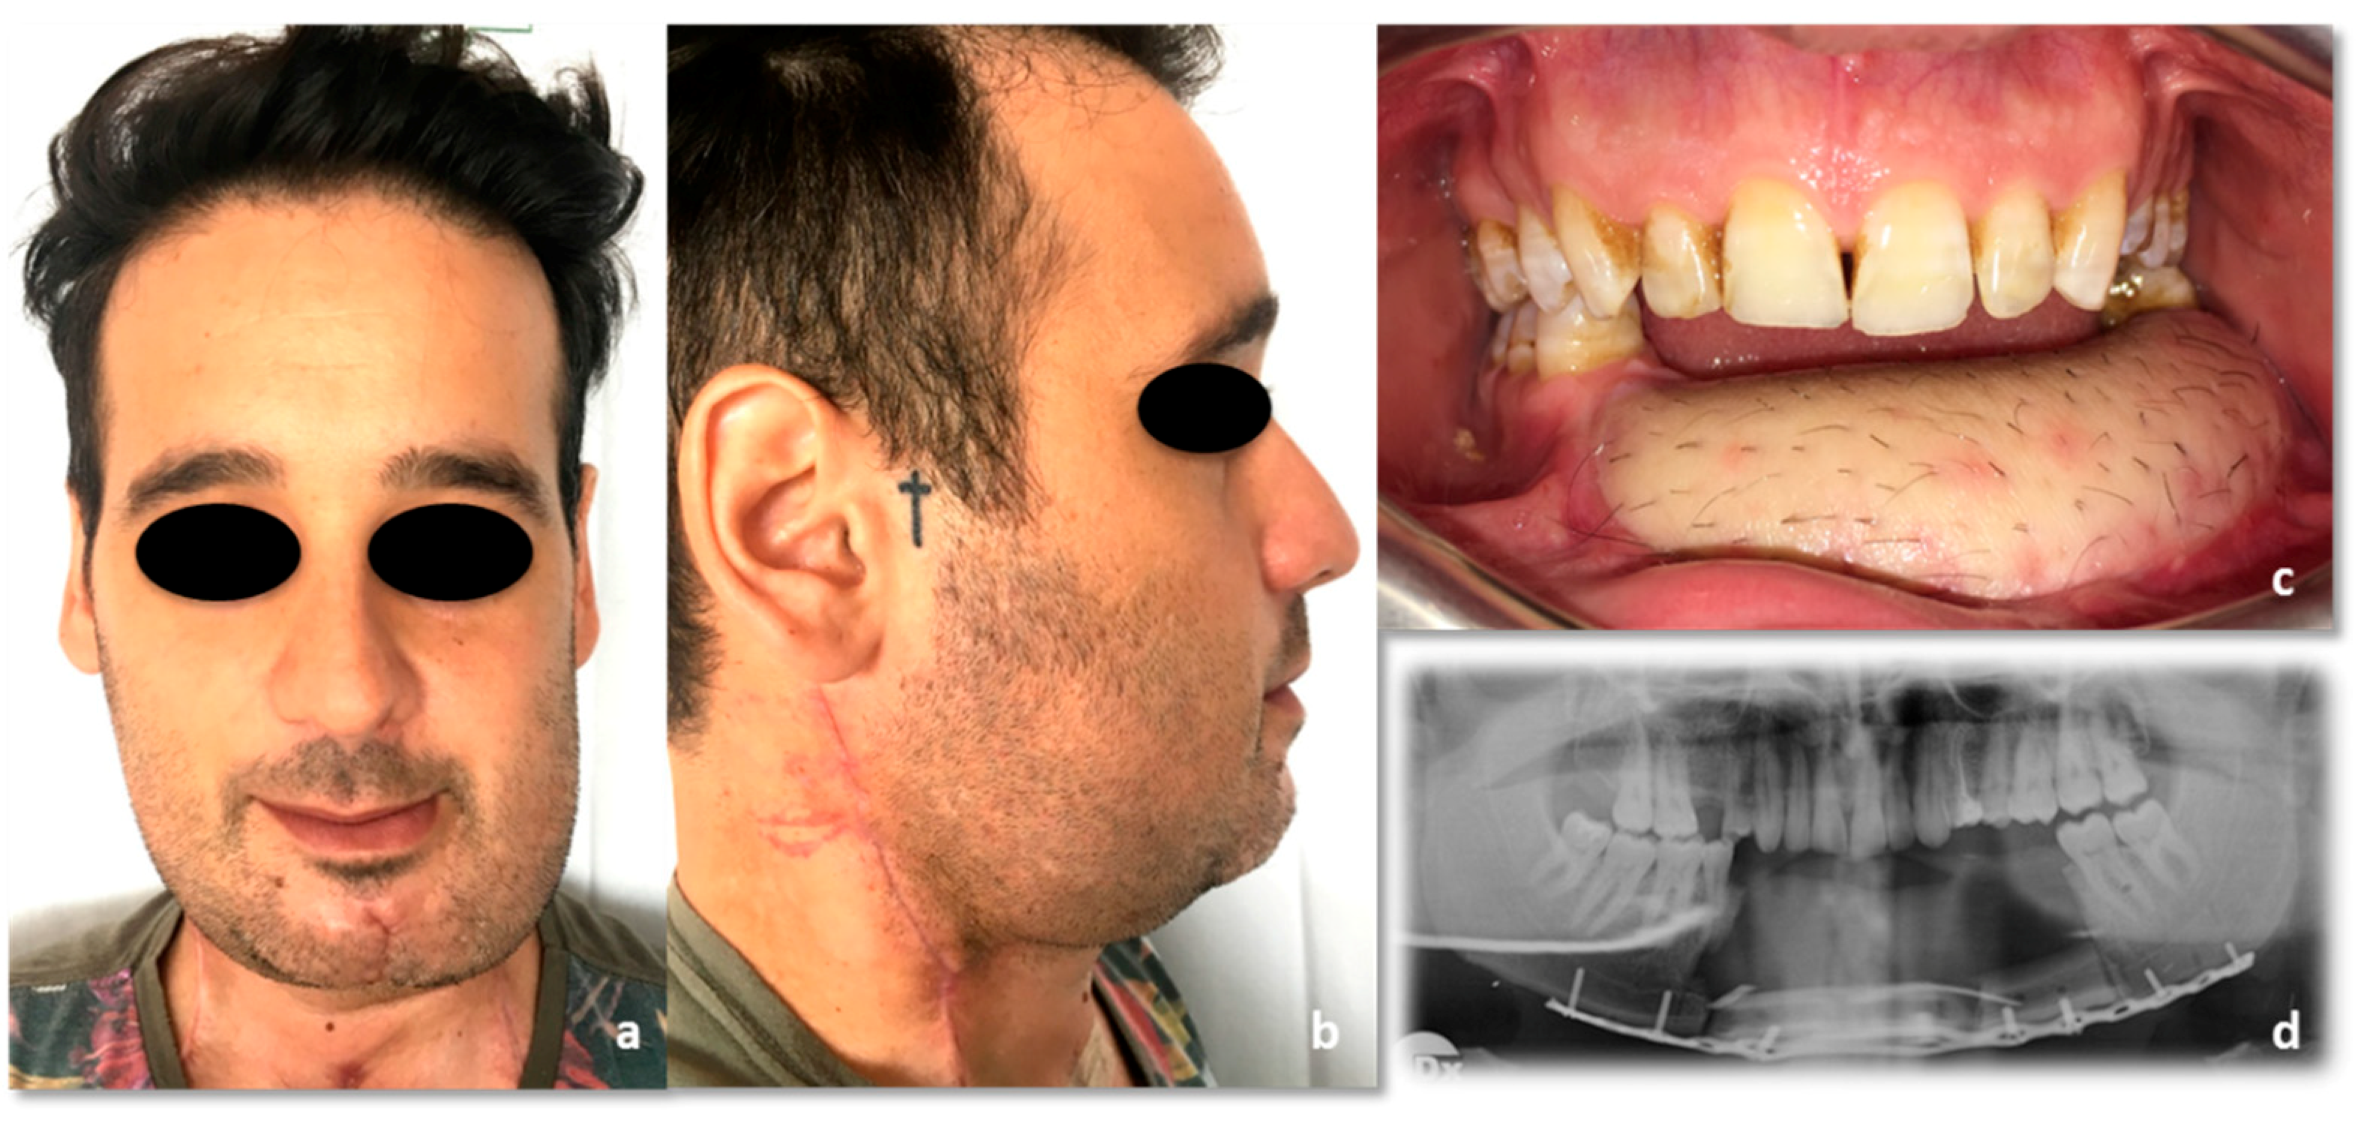

| 2007 | Incidental finding of radiolucent lesion around left impacted lower canine * | Private dentist’s indication for cyst removal (not accepted by the patient) |

| January 2017 | Mandibular abscess with pus discharge from fistula in 32 vestibular region | Private dentist’s prescription for Ceftriaxone 1 g IM for 7 days |

| 10 March 2017 | Reinfection | Amoxicillin/clavulanate 1g per OS for 21 days + Ceftriaxone 1g IM for 7 days ** |

| 22 April 2017 | Reinfection | Emergency department visit with subsequent hospitalization at Cranio-Maxillo-Facial Unit University Hospital of Modena and Reggio Emilia |

| 26 April 2017 | - | Incisional biopsy |

| 22 May 2017 | Admission of the patient and surgical intervention | Segmental mandibulectomy (Type C defect according to Jewer et al. [18] and Type IB according to Cordeiro [19,20] + elective bilateral lymph node (levels I-III) neck dissection + reconstruction with osteo-septo-cutaneous free fibula flap |